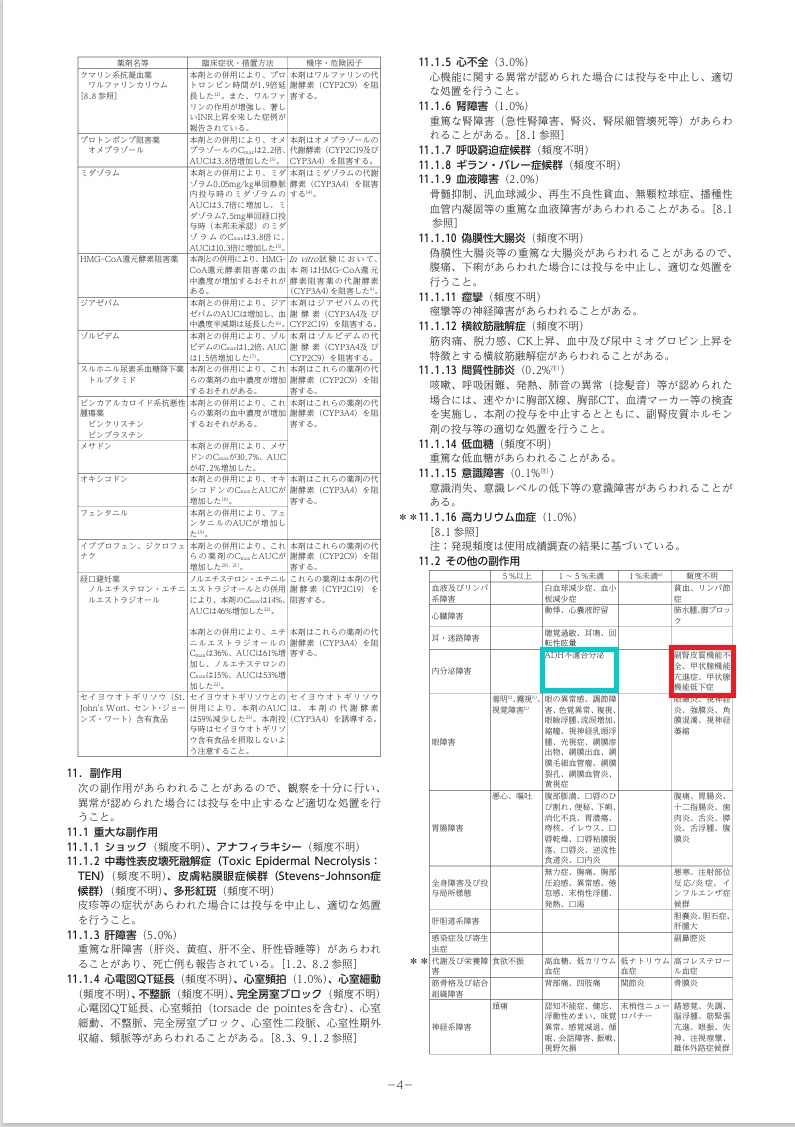

ボリコナゾールは、侵襲性肺アスペルギルス症・アスペルギルス甲状腺炎、カンジダ血症/食道カンジダ症、クリプトコックス髄膜炎/肺クリプトコックスなど深在性真菌症(カビ)の治療薬です。

重篤(重症)な肝障害は有名ですが、副腎皮質機能不全、甲状腺機能亢進症、甲状腺機能低下症(頻度不明)、SIADH(抗利尿ホルモン不適合分泌症候群)(1~5%未満)も引き起こします(添付文書より)。